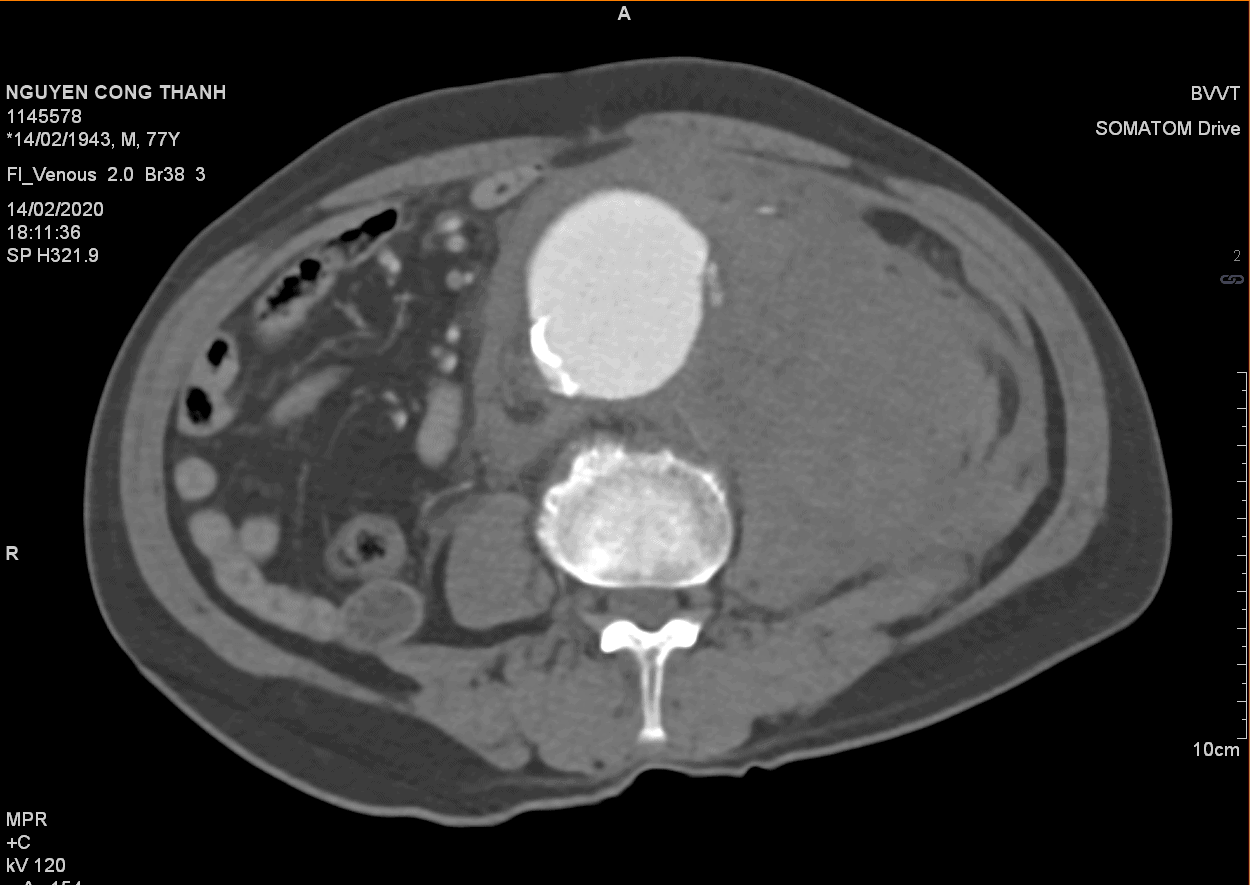

Vỡ phình ĐM chủ bụng

Vỡ phình ĐM chủ bụng - Ảnh 5

» Thông tin: Nam giới – 77 tuổi.

» Lâm sàng: Đau bụng cấp.